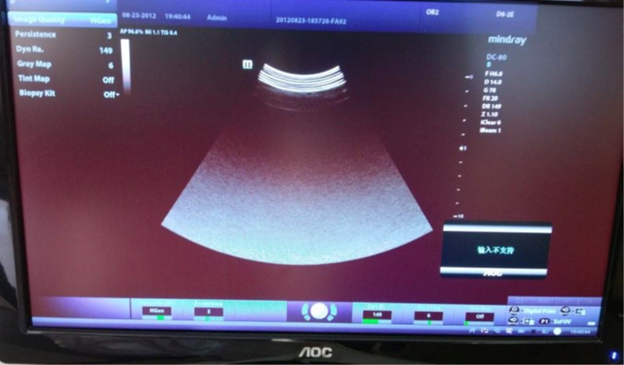

⚠️ Проблема: Во время работы на узи сканере Миндрей DC-80, сенсорный экран отображается зеленым цветом, но его сенсорная функция работает нормально, как показано ниже:

💡 Причина: В данном случае питание сенсорного экрана в порядке. Повторное подключение кабеля сенсорного экрана не решает проблему, соответственно, дефект заключается в самом сенсорном экране.

✅ Решение: Замените сенсорный экран.